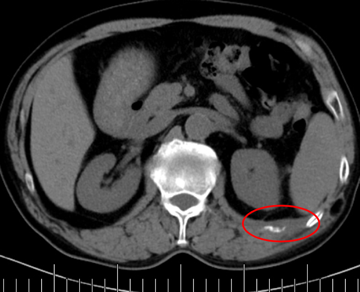

灌注藥物及栓塞后“烏云”消失

肋間動(dòng)脈阻斷營(yíng)養(yǎng)來源

當(dāng)日痛疼緩解